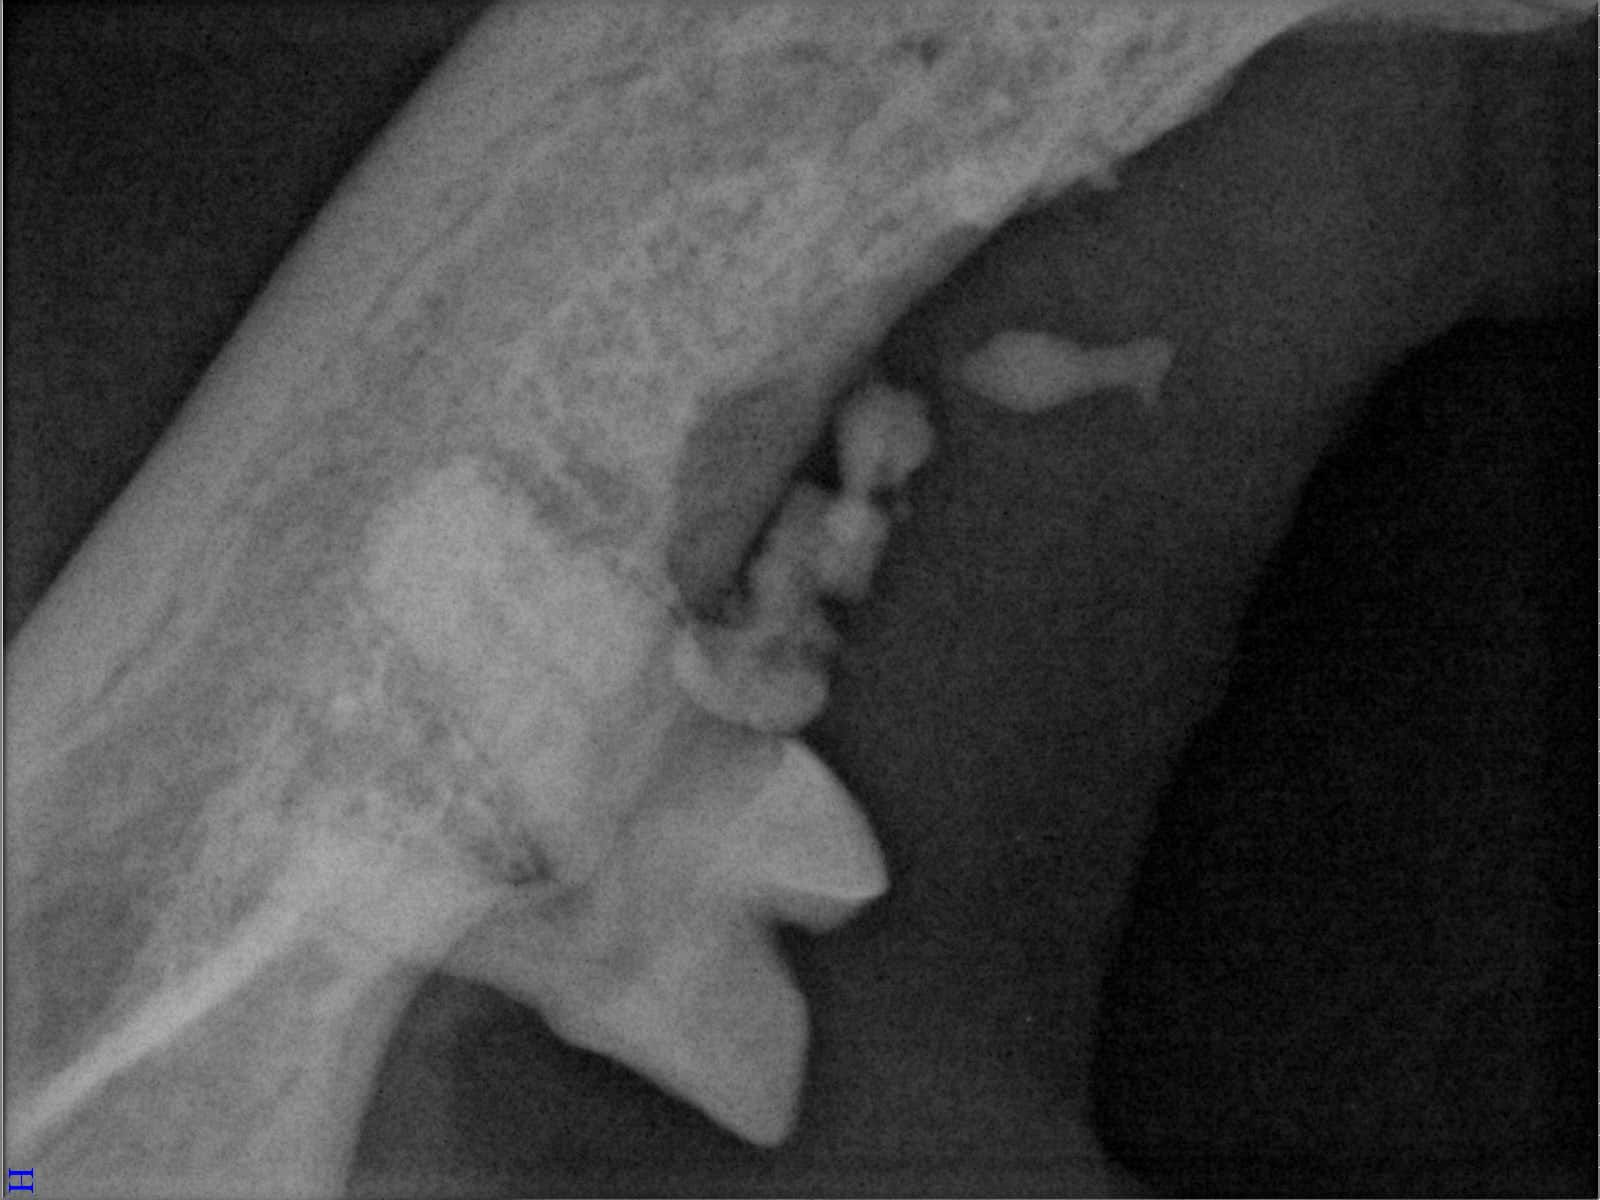

Ein entscheidender Baustein der FORL-Diagnostik ist das dentale Röntgen. Viele Läsionen sind von außen nicht sichtbar und lassen sich ausschließlich mithilfe moderner Röntgentechnik erkennen. In der Hamburger Praxis kommt digitales Dentalröntgen zum Einsatz, das detailreiche Aufnahmen bei geringer Strahlenbelastung ermöglicht. So kann FORL bereits in frühen Stadien diagnostiziert werden.

Das sehen Sie von außen – so sieht es auf den Röntgenbildern aus.

FORL Katze Röntgenbild

Röntgenbilder